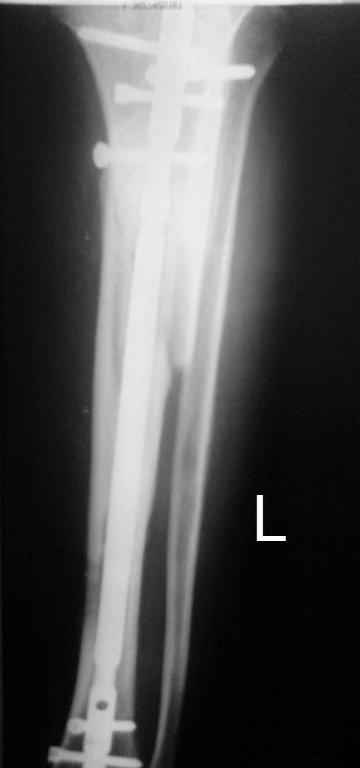

Кратко: мужчина за 60 лет получил травму 28 лет назад (переехало автобусом). Оперировался десятки раз, в итоге с очередным патологическим переломом, хронической язвой и гипсовой лонгетой попал ко мне... Объективно - остеомиелит, инфицированный ложный сустав (или как его назвать), флегмона по наружной поверхности

голени, укорочение около 5 см.

На операции резекция 8 см, внешний остеосинтез,одновременное сближение примерно на 4 см, а затем постепенное сближение до полного контакта в течение 3 недель. Рана с патологически измененными краями, имевшая на операции размеры примерно 4-5 на 10-12 см закрылась самостоятельно в течение примерно 2-х мес. Ну не самостоятельно, конечно, а с нашей помощью, но без пластики.

Сейчас в аппарате вытянул около 6 см в верхней трети.